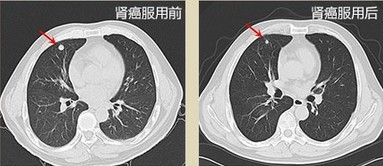

• 灵芝孢粉,把我的肾癌控制住了!湖南,张先生,43岁,6年I期肾癌 2009年的一天,正在上班的我突然感到腰部十分疼痛,被同事送到附近医院,监察发现我得了I期肾癌!后走在长达6年的求医之路,病情依然没有好转,2013年6月,我又去医院接受检查,检查后分析专家说由于我的身体长时间处于疲劳状态,体内激素代谢失调,神经系统功能絮乱,免疫力低下,病情严重。后来另一个也得了肾癌的朋友给我推荐了灵芝孢粉,说这个能克制癌细胞,同事极大的提高免疫力,我服用了3个月的灵芝孢粉,再去检查时竟然发现肾功能好转,现在食欲增加了,精神状态也有了很大的改善,晚上睡觉情况也好。